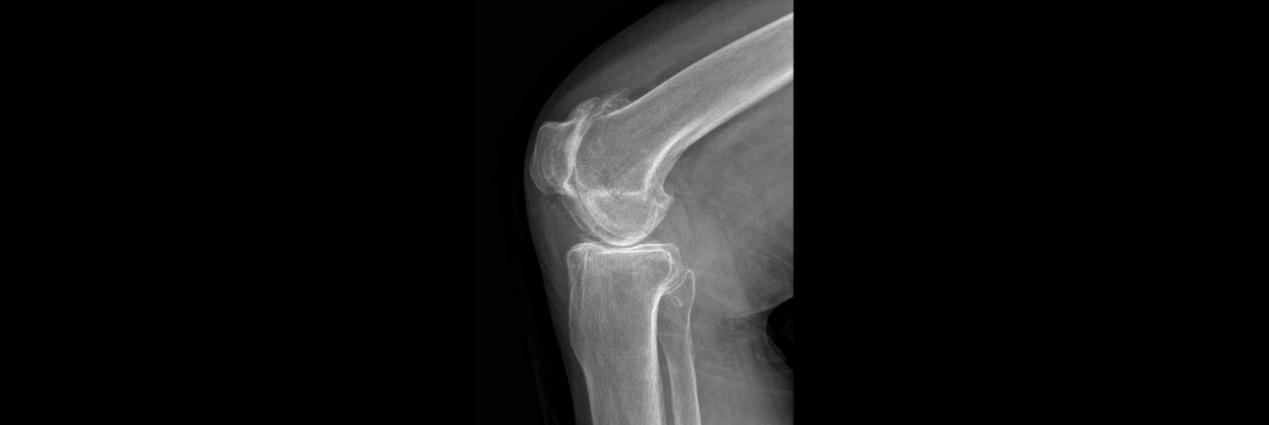

术后

术中,见患者膝关节软骨磨损严重,更换全膝关节假体。术后指导功能锻炼,术后第1天患者便可下地活动,术后3天已无需助行器自行活动,膝关节疼痛明显减轻,患者对手术效果非常满意,现已顺利出院。